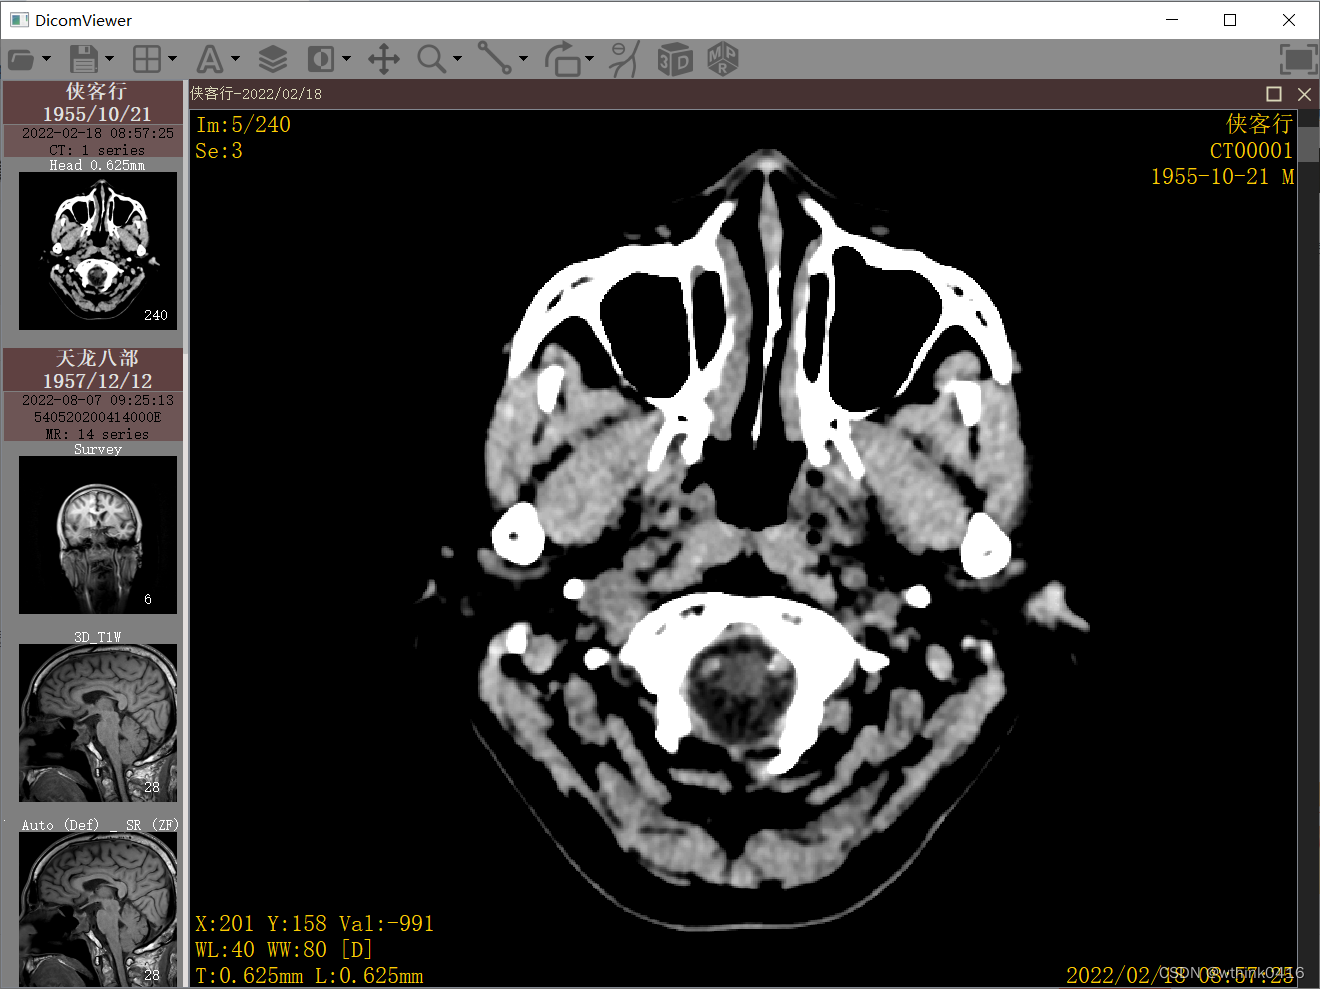

2、选择工具栏的分格图标,可以对图像显示区域进行调整,在每个图像窗口中双击可以实现最大化和还原

3、点击工具栏中A图标,可以实现隐藏和显示四角信息,同时下拉菜单包含显示该图像的所有Tag值,以及隐藏患者信息等功能,Tag值显示界面左下角可根据输入进行筛选。

5、点击![]() 调整窗宽窗位图标后,鼠标左键按下同时移动,左右移动调整窗宽,上下移动调整窗位,下拉菜单可预设一些窗宽窗位

调整窗宽窗位图标后,鼠标左键按下同时移动,左右移动调整窗宽,上下移动调整窗位,下拉菜单可预设一些窗宽窗位